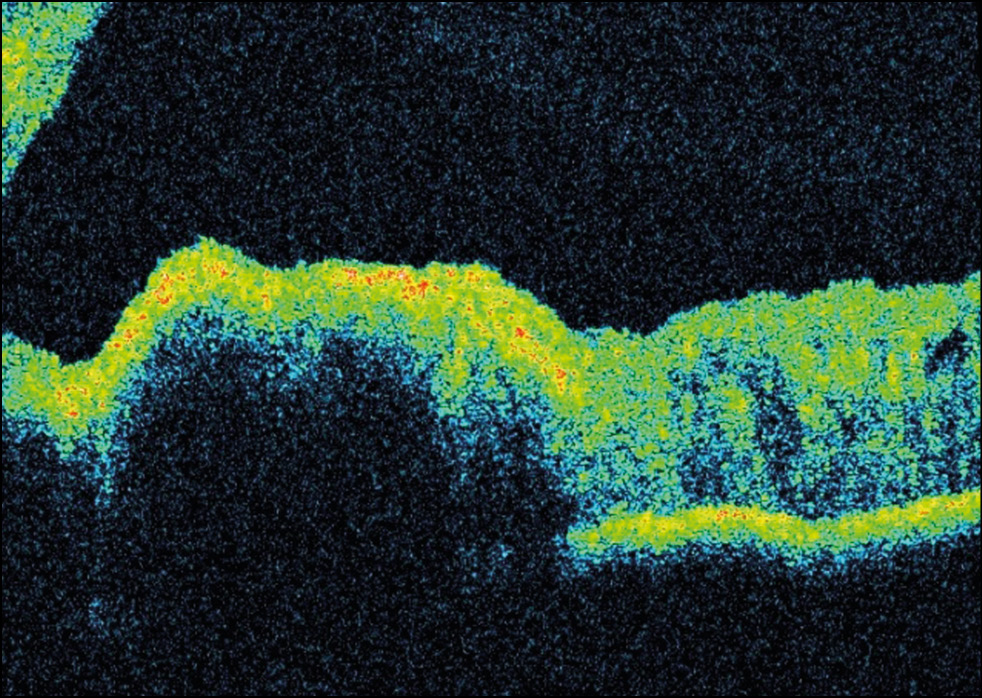

Пациентка А., 13 лет. При диспансерном осмотре по месту жительства в апреле 2021 г. впервые заметили пигментное новообразование радужки левого глаза, обратились в НМИЦ глазных болезней им. Гельмгольца (Центр). Обследована в поликлиническом отделе, острота зрения OS с диафрагмой составила 0,4–0,5. Выполнена ультразвуковая биомикроскопия левого глаза: в нижне-внутреннем квадранте отмечено локальное утолщение зоны с проминенцией 0,9 мм и диаметром основания 2,06×2,02 мм с повышенной акустической плотностью. Профиль задней поверхности радужки неровный. Установлен диагноз пигментное новообразование радужки левого глаза без признаков активности, рекомендовано динамическое наблюдение с контрольным осмотром в Центре через 6 месяцев (рис. 12).

Рис. 12. Пигментное новообразование радужки.

При контрольном осмотре в декабре 2021 г. выполнена повторная ультразвуковая биомикроскопия левого глаза, в результате чего было выявлено увеличение диаметра основания 2,5×2,11 мм образования по сравнению с первым осмотром 2,06×2,02 мм (рис. 13).

Рис. 13. Ультразвуковая биомикроскопия радужки OS.

Клинически определена отрицательная динамика в связи с наличием признаков роста и распыления пигмента вокруг образования.

С помощью оптической когерентной томографии определяется гиперрефлективная поверхность образования с эффектом «тени» подлежащих структур (рис. 14).

Рис. 14. Оптическая когерентная томография радужки OS. Гиперрефлективная поверхность образования.

Пациентке проведена иридэктомия с иридопластикой. После операции острота зрения OS с диафрагмой составила 0,4–0,5. Гистологическая картина соответствовала веретеноклеточному невусу. Пациентке рекомендовано динамическое наблюдение.